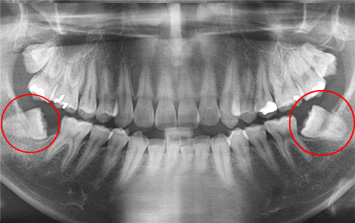

사랑니가 잇몸 속에 누워 인접치아가 깨지고 충치가 발생하여 심한 통증으로 내원한 환자

아래쪽 사랑니 두 개가 심하게 누운 상태로 내원, 오른쪽 사랑니는 인접치아를 누르고 있고 왼쪽 사랑니는 음식물이 잘 끼고 가끔 염증이 생긴다고 합니다.